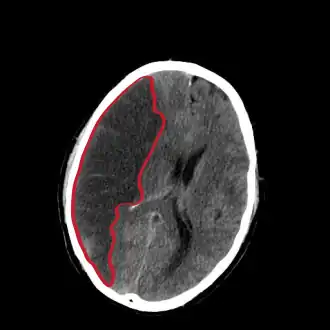

| Corte do cérebro [ostrando um infarto cerebral hemisfério direito (lado esquerdo da imagem). | |